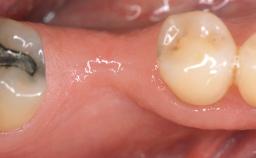

Implant Placement in the Esthetic Zone and Coverage of Multiple Gingival Recessions

This case illustrates use of a modified ‘tunnel’ technique, which has been shown to be highly effective in root coverage procedures. The tunnel technique is used to achieve soft-tissue augmentation across the anterior area, including the planned implant site, using collagen matrix as grafting material. The patient is a 47-year-old woman with high esthetic expectations. Her main concern was the appearance of the anterior teeth and their “elongation”.